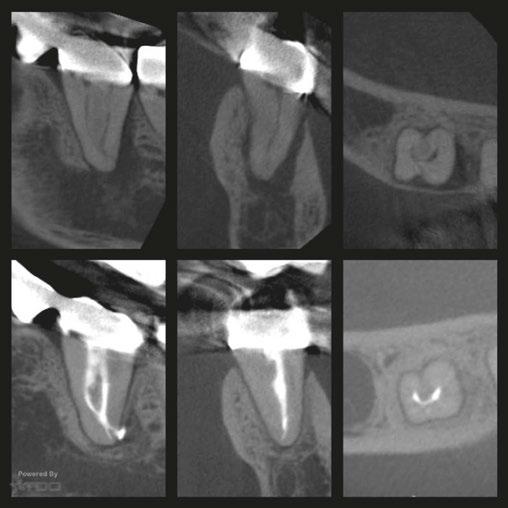

5A-5B: CBCT was taken during initial endodontic exam in 2023. 5A. Coronal CBCT

revealed a 6.1 mm x 3.0 mm hypodensity extending from the apical and distal aspect of No. 11. 5B. Sagittal

slices revealed the presence of bone between tooth No. 11 and implant No. 12

spacing of 3.4 mm between the two was noted (Figure 4). The recommended amount of space between a natural tooth and dental implant should be 1.5 mm-2 mm, proving adequate spacing in this case.15 Coronal views of the CBCT evaluation revealed a 6.1 mm x 3.0 mm hypodensity extending from the apical and distal aspect of tooth No. 11 (Figure 5A). Sagittal slices revealed the presence of healthy bone morphology between the distal border of the hypodensity on tooth No. 11 and implant No. 12, thus the hypodensity did not extend to the implant (Figure 5B). Reference was made to the Treatment Options for the Compromised Tooth: A Decision Guide published by the AAE in 2017 to determine prognosis.16 In evaluating the coronal tooth structure, tooth No. 11 had a well-fitting crown with adequate margins, no need for crown lengthening, and required only routine endodontic treatment placing it in the favorable category. The periodontal condition of tooth No. 11 was also favorable with probing depths equal to or less than 3 mm and a normal periodontium. Lastly, the apical periodontitis was expected to resolve following non-surgical root canal treatment.16 Thus, tooth No. 11 was diagnosed as pulpal necrosis with asymptomatic apical periodontitis with a favorable prognosis. Nonsurgical root canal treatment was planned, and informed consent was obtained.

Figure 4: Sagittal CBCT slice revealed 3.4 mm of space between the apex of tooth No. 11 and the mesial border of implant No. 12

USA, Savannah, Georgia) and gutta percha via continuous wave condensation. EndoSequence BC liner blue (Brasseler USA, Savannah, Georgia) was placed over the gutta percha at the canal orifice, and the tooth was temporized using a cotton pellet and Fuji IX placed in the access (Figure 6). Following completion of the root canal, the patient was scheduled for a 3-month reevaluation and referred to her provider for definitive restoration. Healing was observed at the 3- and 6-month postoperative visits. Periapical radiographs were exposed at each visit revealing bony healing (Figure 7). The patient reported no pain or symptoms following nonsurgical root canal treatment. At both visits, percussion and palpation were negative. A CBCT was captured at the 6-month postoperative exam to evaluate healing. Coronal CBCT slices revealed a reduction in lesion size to 3.5 mm x 1.6 mm. Sagittal slices also showed reduction in lesion and maintained health of bone surrounding implant No. 12 (Figure 8). A 2011 article by Ng outlines eleven factors that, if present, improve periapical healing following primary non-surgical root canal treatment.17 Only two of these eleven factors, absence of a preoperative periapical lesion and size of the preoperative periapical lesion, were not met in this case report. Along with this and the 2017 AAE Treatment Options for the Compromised Tooth: A Decision Guide article, the final prognosis for healing is favorable.16

Figures 8A-8B: CBCT was taken at the 6-month postoperative visit. 8A. Coronal CBCT slices revealed a reduction in lesion size to 3.5 mm x 1.6 mm. 8B. Sagittal CBCT slices revealed a reduction in lesion size and maintained health of bone surrounding implant No. 12